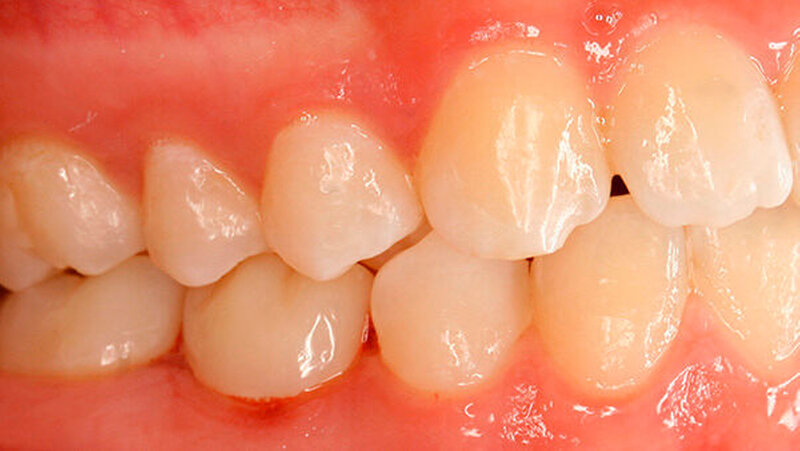

Die Patientin zeigte ein kariesfreies bleibendes Gebiss mit Nichtanlage des Zahns 35 und Persistenz des Zahns 75 auf (Abbildung 1). Sie wies im Frontzahnbereich sowie im rechten Seitenzahnbereich eine Klasse I auf, im linken Seitenzahnbereich aufgrund der Größe des Zahns 75 eine Klasse II. Zahn 75 befand sich in deutlicher Infraokklusion (Abbildung 2). Der Perkussionstest wies allerdings nicht eindeutig auf eine Ankylosierung hin.